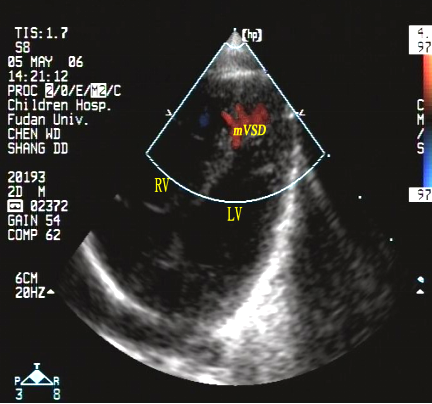

室间隔缺损(肌部,多发性)

经食管超声心动图监测肌部室间隔缺损镶嵌治疗